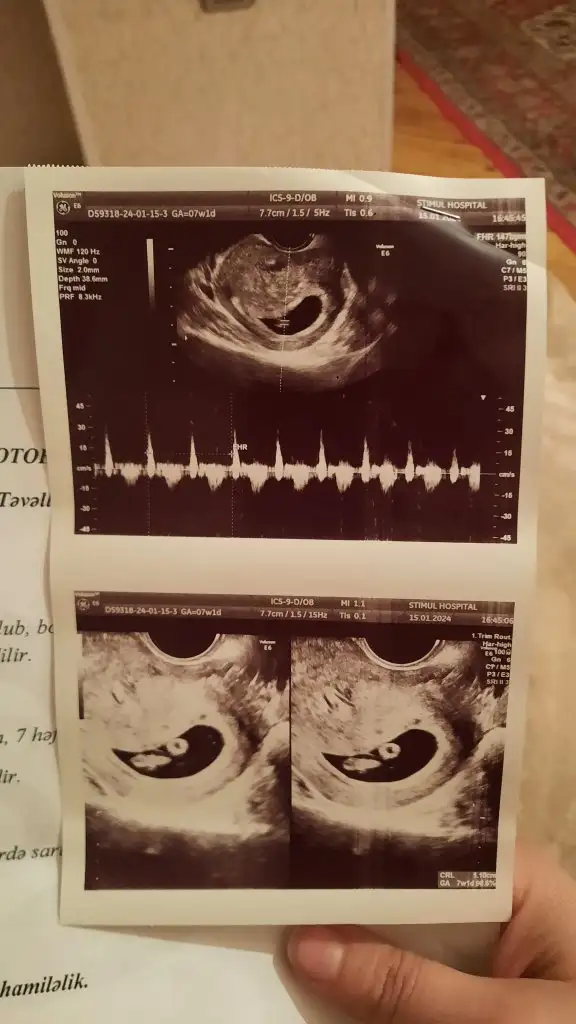

Karından çekildi 6 haftalık yorumlarmisin lütfenErkek canım

Ramzi teorisine göre ( bilimsel bir araştırma sonucuymuş ve %85 doğruluğu varmış). İlk 6-8 haftalık ultrason görüntüsüne göre bebeğin kesenin içersinde soldan ya da sağdan girişine göre cinsiyet tahmini yapılıyor. Bilimsel olunca tecrübeli annelerimiz yada anne adaylarımızdan yardım istiyoruz. Doğruluğu var mı öğrenmek adına :) Bizleri aydınlatırsanız çok seviniriz. bu teorieye göre;

Vajinal muayeneyle bakıldıysa eğer;

Sağdan girmiş gözüküyosa aslında solmuş ve ERKEK,

Soldan girmiş gözüküyosa aslında sağmış ve KIZ ,

Karından bakıldıysa eğer,

Soldan girmiş gözüküyosa gerçektede solmuş ve ERKEK,

Sağdan girmiş gözüküyosa gerçekte de sağmış ve KIZ,

Bu ultrason karındansa eğer bebek kız olabilir.

7+1 tahmin yapabilir misiniz Hülya hanımCanîm kıza çok benziyo hayırlısı olsun inşallah senne hissediyosun

Burada bebeğin konumununa göre yorum yapmışlar ama ramzi teorisi plasentanın konumuna göre bilgi veriyor diye biliyorum ben. Plasentanın da nerede olduğunu göremedim 2 gündür:)Konu biteli yıllar olmuş ama belki yorum gelir 7+4 karındanEki Görüntüle 3454856